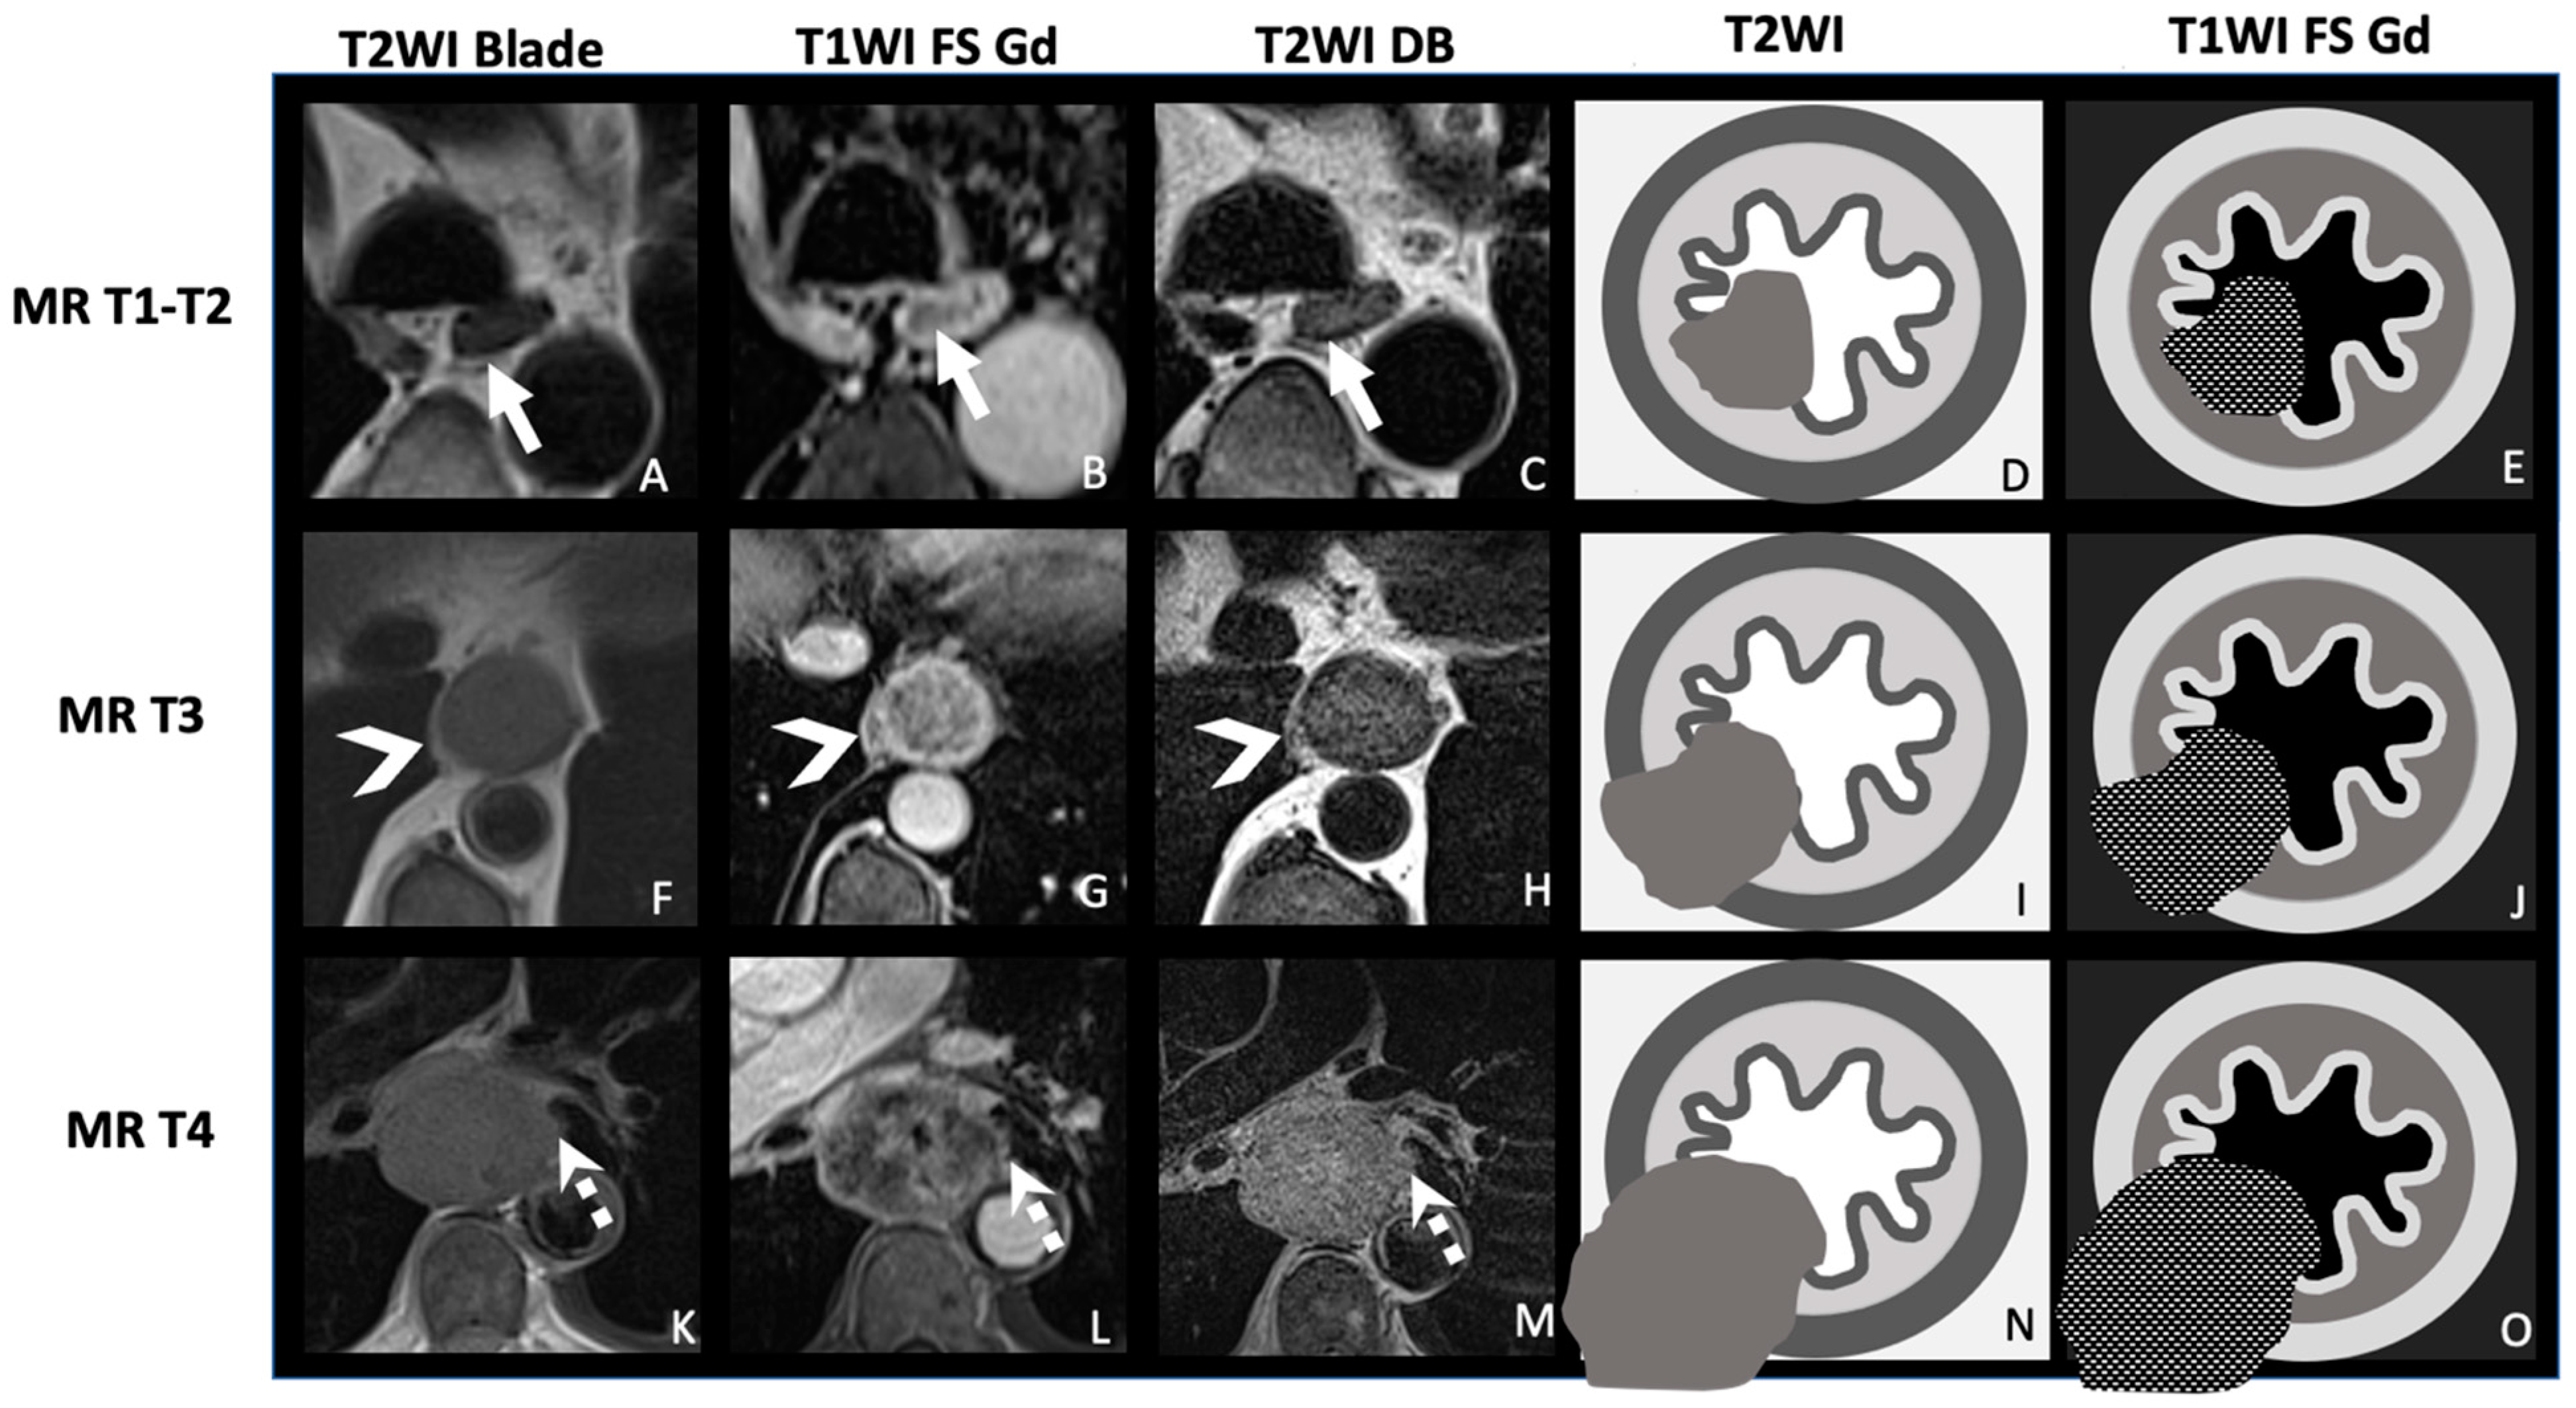

| TNM Histo-Pathologi Definition (According to AJCC/UICC 8th Edition) | MRI TNM Staging |

| T1: Tumor invades the submucosa | MR-T1-T2: Tumor signal intensity is confined to esophageal wall without extension to peri-esophagus fat |

| T2: Tumor invades the muscularis propria | |

| T3: Tumor invades adventitia | MR-T3: Tumor invades the peri-esophagus fat tissue |

T4: Tumor invades adjacent organ

| MR-T4: Tumor invades adjacent organs